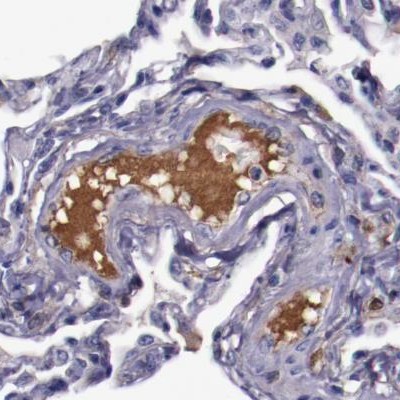

Immunohistochemical staining of human colon, kidney, lung and lymph node using Anti-APOH antibody HPA001654 (A) shows similar protein distribution across tissues to independent antibody HPA003732 (B).